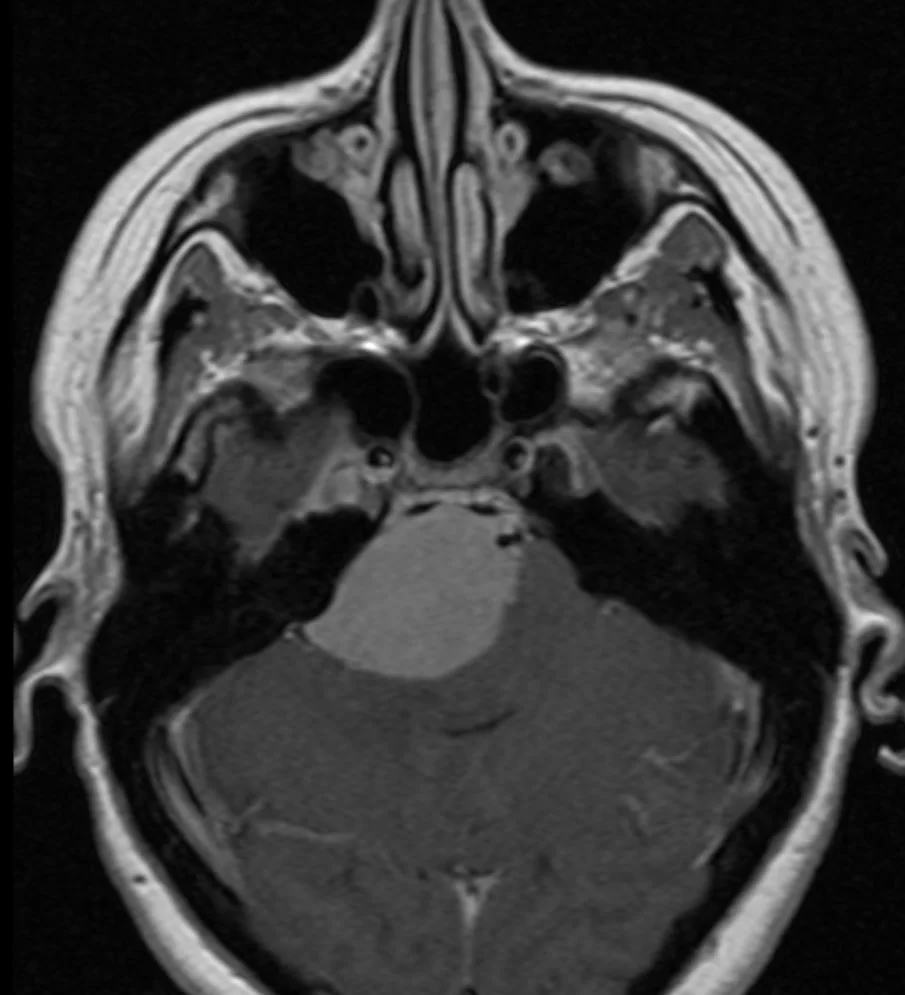

Ο απεικονιστικός έλεγχος με μαγνητική τομογραφία ανέδειξε ευμεγέθη όγκο με επέκταση τόσο στον μέσο όσο και στον οπίσθιο κρανιακό βόθρο και σημαντική πίεση επί του στελέχους, συμβατό με μηνιγγίωμα του λιθοειδούς-αποκλίματος.

Διενεργήθη συνδυασμένη υποκροτάφιος – προσιγμοειδική προσπέλαση.

Η μετεγχειρητική αξονική τομογραφία εγκεφάλου δείχνει σημαντική μείωση του όγκου, με ελάχιστα υπολειμματικά στοιχεία στην περιοχή του σηραγγώδους κόλπου δεξιά. Η ιστολογική εξέταση ανέδειξε μηνιγγίωμα (WHO I).